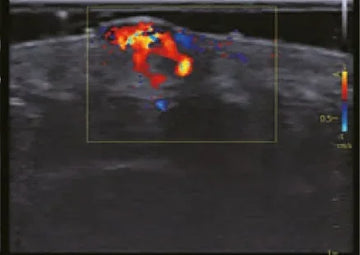

- Vascular: detección de trombos, obstrucciones o problemas de circulación con ecografía Doppler.